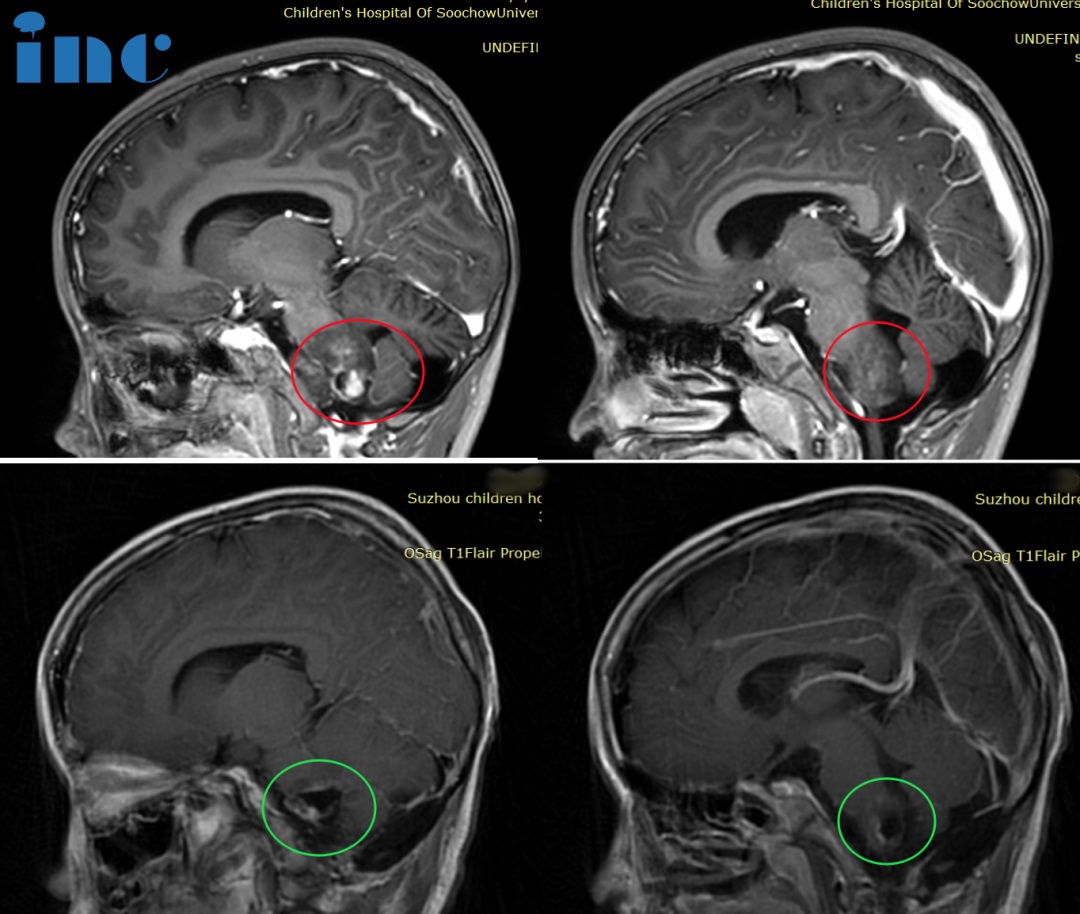

◉患者情况:14岁的睿睿2016年底偶发左手抓握力弱,2017年初查出神经节细胞瘤;医生表示肿瘤生长缓慢,无法全切,还会复发,故保守观察。后两年病灶缓慢增大,运动能力减弱。2021年底,双侧肢体无力加重,左侧更明显。2022年睿睿再次就医检查,MRI显示桥脑+左侧小脑+颈3以上不规则信号,然而由于肿瘤位于脑干延申至脊髓,肿瘤占位大小33*42*94mm。在国内某医院做了一开始开颅手术,虽仍有不少残留,但手术取得完整病理,肿瘤导致的病情有适当好转,为后续手术提供了清晰的思路、争取了时间……

◉治疗经过:2022年巴教授中国疑难示范手术期间,睿睿父母咨询巴教授能否为孩子顺利手术,“我之前找的主刀医生也都......但教授明确的告诉你最大的风险在于四肢瘫痪,同时他明确的告知全瘫痪的风险是1%。“ ,2022年11月16日,在苏州大学附属儿童医院,巴教授为睿睿进行了手术,全程呼吸、心跳平稳,手术顺利,无新发后遗症。术后2天顺利转出ICU。

◉术后情况:术后11天,巴教授查房时,睿睿已经可以在父母的搀扶下站起来。当教授询问睿睿,“吞咽怎么样?”时,睿睿也能够亲自回答“可以……”!看到孩子睿睿的这么好,巴教授不由得竖起大拇指点赞“Very Good!”